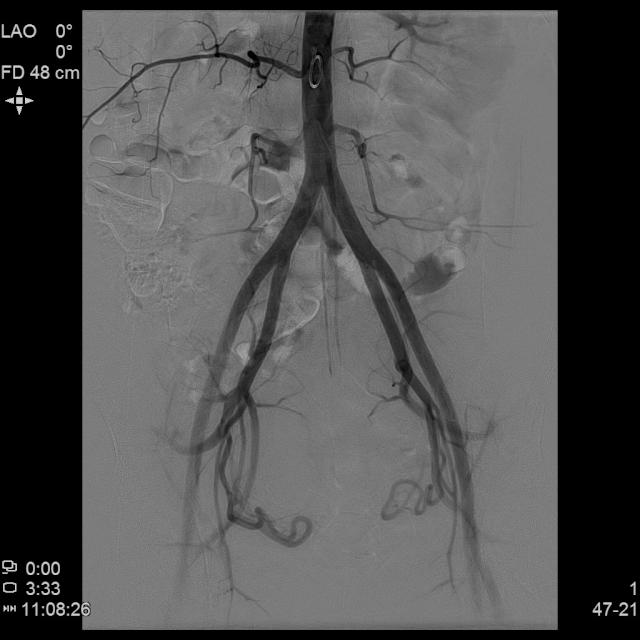

经桡动脉入路UAE治疗,除操作入路不同外,与常规股动脉入路UAE相似,可大大提升患者术后舒适度!

- 经桡动脉鞘置入猪尾巴导管造影显示双侧子宫动脉明显增粗,染色丰富,子宫明显增大

- 进一步超选插管右侧子宫动脉造影确认位置

- 进一步超选插管左侧子宫动脉造影确认位置